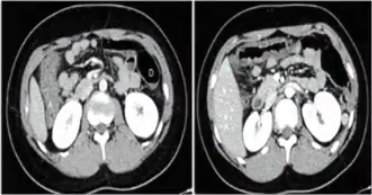

患者以便血、急腹症为主,之后于急诊就诊。CT显示升结肠、横结肠水肿,肠壁增厚。

1605003341958114.png